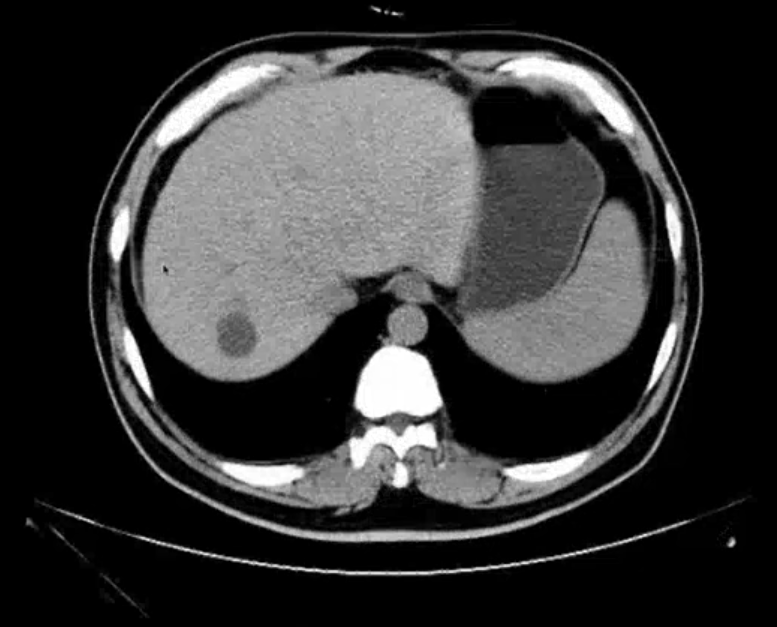

肝CT

- 40~60HU,高于胰,脾

- 肝内管道系统(胆管,肝动脉静脉和门静脉)低于实质,周围小分支多不显示。大血管呈低密度树状影

- 囊肿:

- 壁薄。有张力 -> 边界清晰

- 内部液体密度:<10HU,类似胃密度

- 内部密度均匀

- CTA不强化